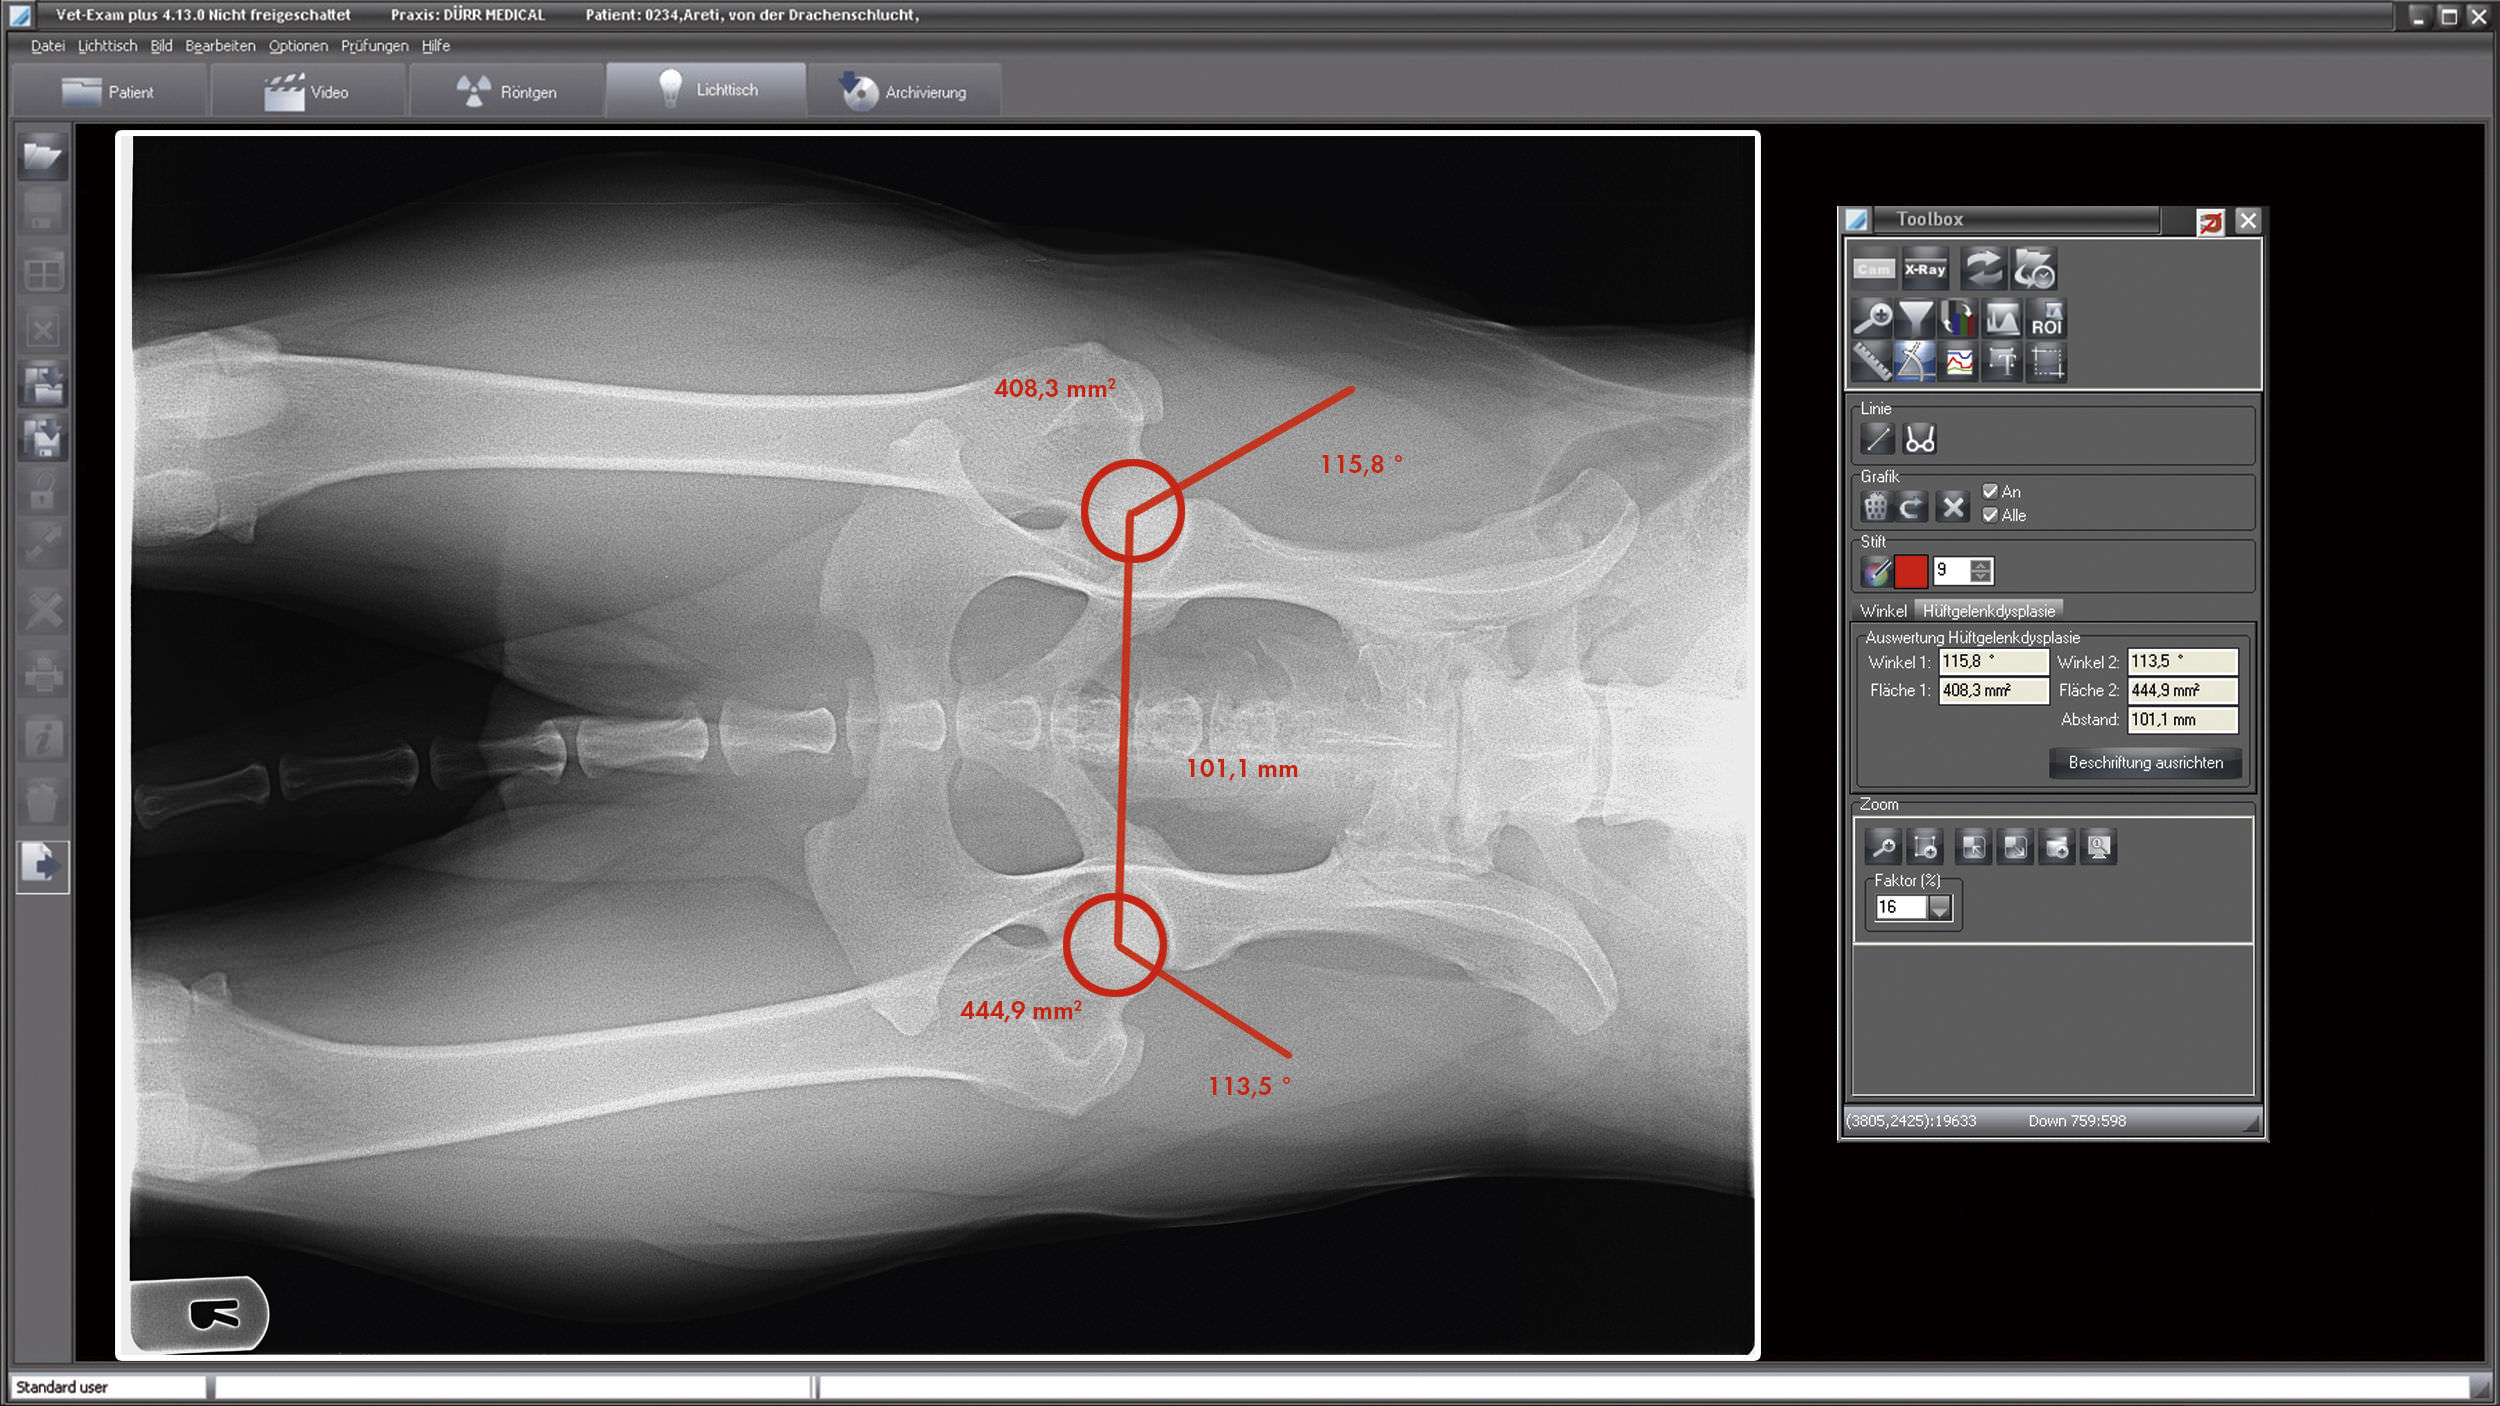

From www.medicalexpo.com

Acquisition software / for veterinary radiology / medical VETEXAM Radiology Vet Consulting dvm stat consulting's telemedicine service is for veterinarians in the us and canada. our radiology service is pay per case and our consulting service can be either pay per case or monthly subscription, which gives you unlimited access to. our radiology service is pay per case and our consulting service can be either pay per case or. Radiology Vet Consulting.